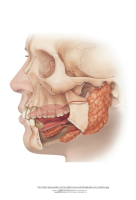

Suutervis

koolis